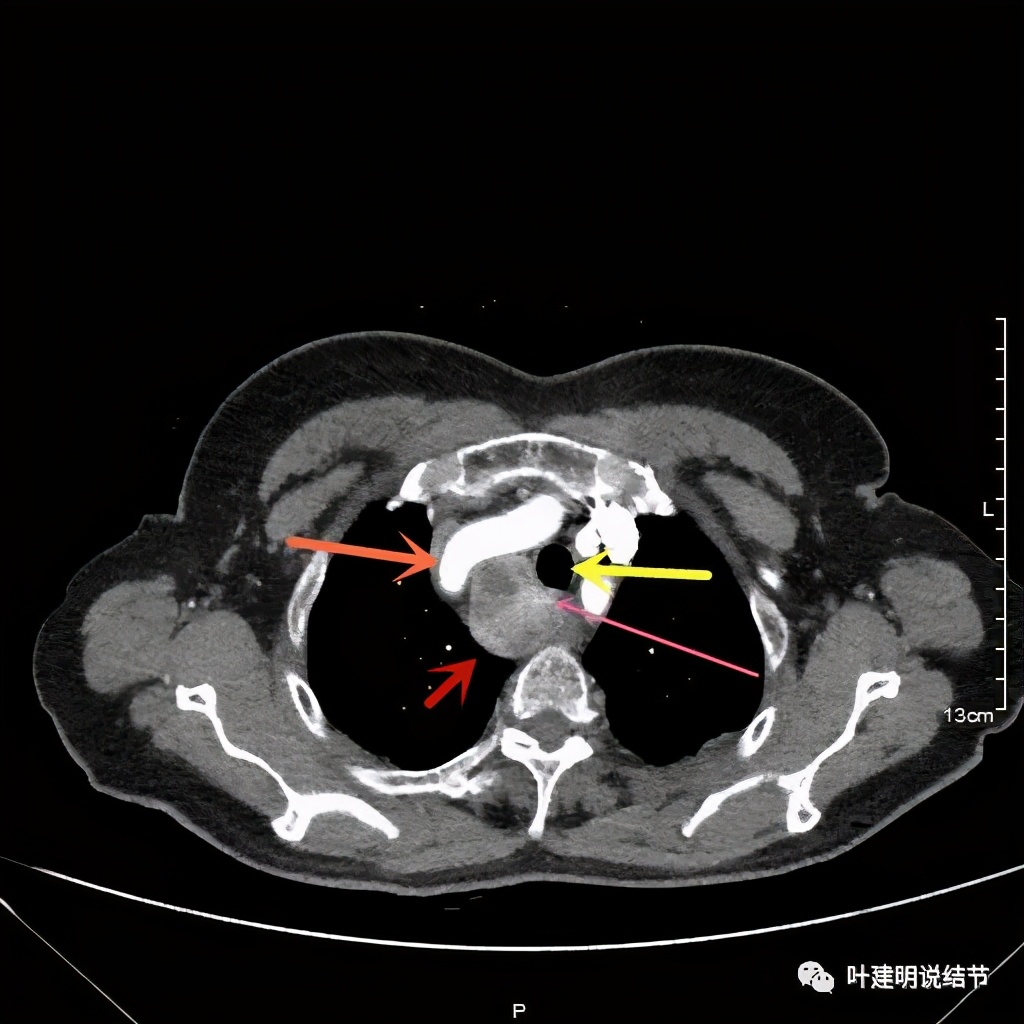

上图红色示肿瘤,粉色示肿瘤与气管关系密切,而且肿瘤密度不均杂乱

上图红色示肿瘤,黄色示气管,粉色示肿瘤与气管关系密切,而且肿瘤密度不均杂乱